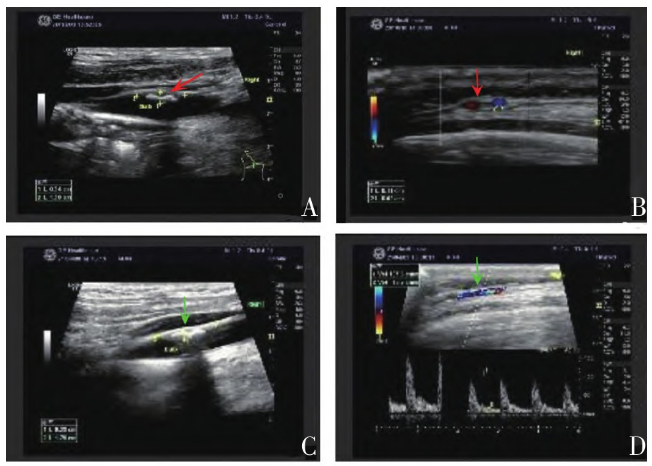

(polymyalgia rheumatica,PMR)。血管超声提示双侧颈动脉、颈总动脉炎性病变可能,左颞动脉周边可见“晕环征”,炎性浸润可能(图1A、1B)。

2021年4月6日复查,查体见满月脸;白细胞5.11×109/L,C反应蛋白0.398mg/dl,ESR 11mm/h,Ig M26.1mg/dl;肝肾功能正常;血管超声(图1C、1D)示颞动脉“晕环征”消失;18F-FDG-PET/CT示:主动脉、双侧头臂动脉-锁骨下动脉-肱动脉、髂动脉及股动脉上段代谢较前减低(图2B),腰2-5双侧椎小关节代谢增高区消失,双侧坐骨结节及双髋关节周围软组织代谢减低,颈6椎体左侧局部高代谢消失(图2B、3B、3D、3F)。患者症状明显好转,食欲佳,体重增加约5kg。继续予醋酸泼尼松龙片(15mg,qd)口服治疗,每2周减少2.5mg。患者后未诉明显不适,规律复诊。

图1 患者治疗前后颈部血管彩色多普勒超声。A.治疗前双侧颈动脉内膜增厚伴斑块形成,双侧颈总动脉内膜增厚;B.治疗前双颞动脉流速增快,左颞动脉周边可见“晕环征”,炎性浸润可能;C.治疗后双侧颈动脉内膜增厚伴斑块形成,右颈动脉内中膜稍增厚,颈部动脉流速增快;D.治疗后双侧颞动脉未见“晕环征”。

影像学是GCA诊断和鉴别的重要线索。彩色多普勒超声具有无辐射、接受度高、经济便捷等优势,颞动脉超声提示“晕征”血管狭窄甚至闭塞时,可以对临床诊断起到提示作用,有研究表明出现单侧“晕征”时诊断GCA的敏感度和特异度分别为68%和91%。

本例颞动脉超声提示单侧“晕环”征及动脉血管壁增厚,故进一步行18F-FDG-PET/CT检查,表现为动脉管壁广泛性、弥漫性增厚伴不均匀葡萄糖摄取增高,具有一定的特异性,再次复诊时,PET/CT影像结果表明患者病情好转,血管炎症性病变程度减轻,疾病活动性降低。本例患者确诊后给予大剂量糖皮质激素联合环磷酰胺治疗,症状缓解迅速,并持续小剂量糖皮质激素维持治疗。随访至今,预后良好。